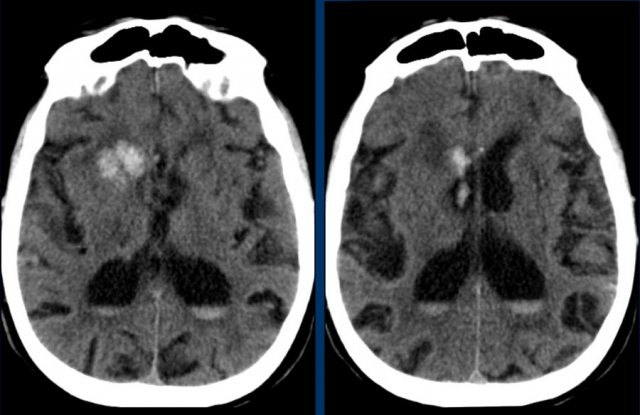

The subarachnoid hemorrhage (SAH) stages. The yellow arrows

SAH causes capillaries to narrow, blocking RBC movement. (a) Left

The subarachnoid hemorrhage (SAH) stages. The yellow arrows indicate

The subarachnoid hemorrhage (SAH) stages. The yellow arrows indicate